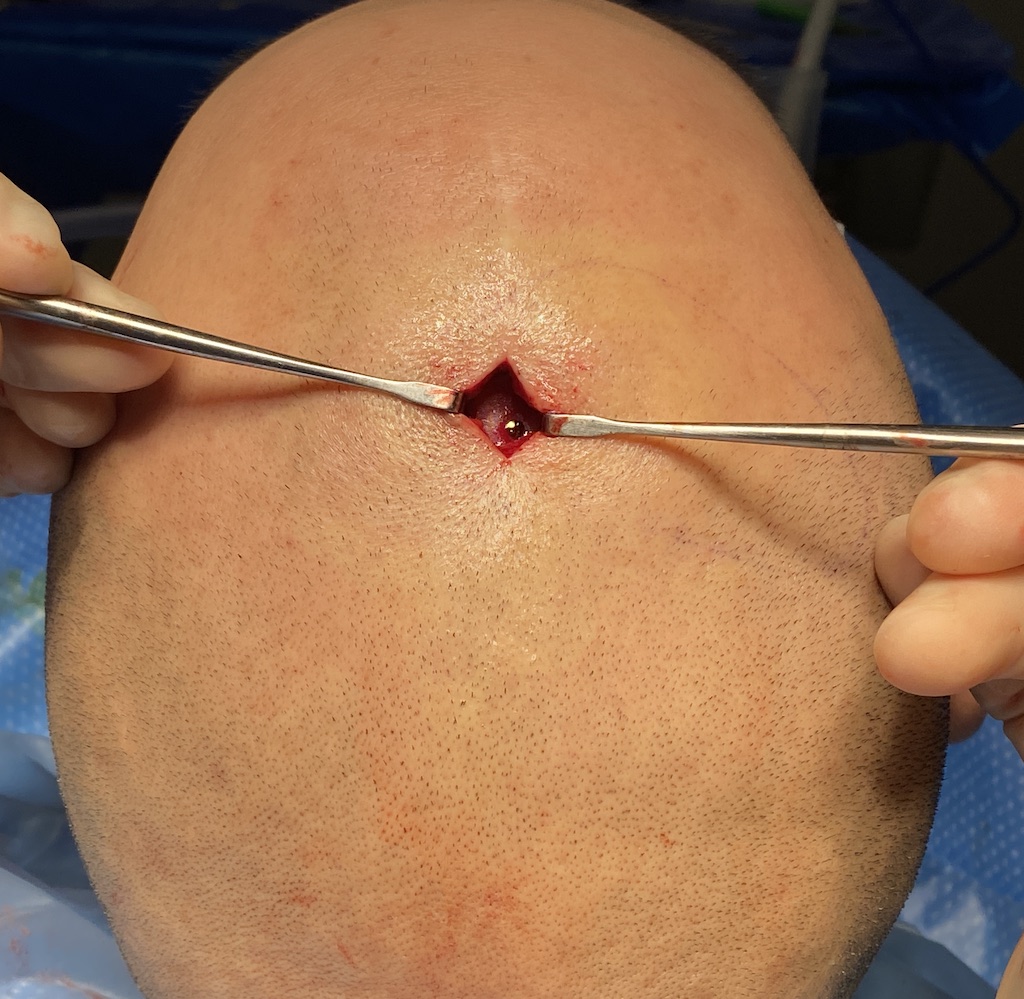

Desire for reduction of prominent occipital knob deformity.

Intraoperative result from occipital knob skull reduction through a direct small scalp incision.

Desire for reduction of prominent occipital knob deformity.

Intraoperative result from occipital knob skull reduction through a direct small scalp incision.